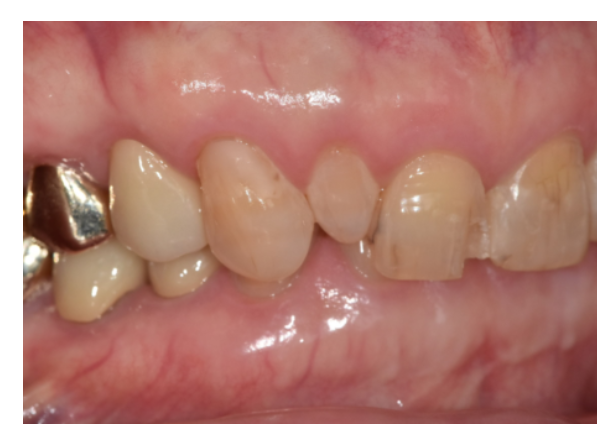

이 환자분도 교정보다는

작은 앞니의 크기를 주변 치아와 맞추고,

앞니 사이 벌어짐과 깨지는 레진 문제를

함께 해결하는 방향이 필요했습니다.

그래서 앞니 라미네이트 치료를

계획했습니다.

이런 과개교합은 라미네이트 치료를 진행할 때

파절 가능성을 최대한 줄이는 것이 가장 중요합니다.

그래서 치아를 많이 깎기보다는

필요한 만큼만 최소한으로 삭제하고,

그 안에서 라미네이트가

안정적으로 자리 잡을 수 있는 공간을 확보하는 것이 핵심입니다.